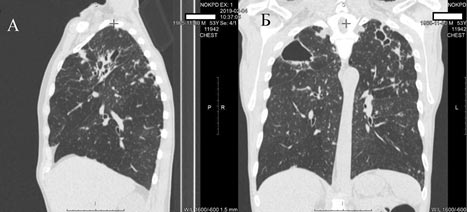

С целью получения достоверных сведений о скиалогических характеристиках патологического процесса в органах грудной клетки пациенту была проведена мультиспиральная компьютерная томография, при которой выявлены признаки диссеминированного процесса, множественные полости распада с тенденцией к формированию фиброзно-кавернозного туберкулёза в верхних долях обоих лёгких, 6-м сегменте справа (рис. 1).

Рис. 1. Мультиспиральная компьютерная томография, снимки пациента от 29.11.2018: А — сагиттальный срез; Б — фронтальный срез